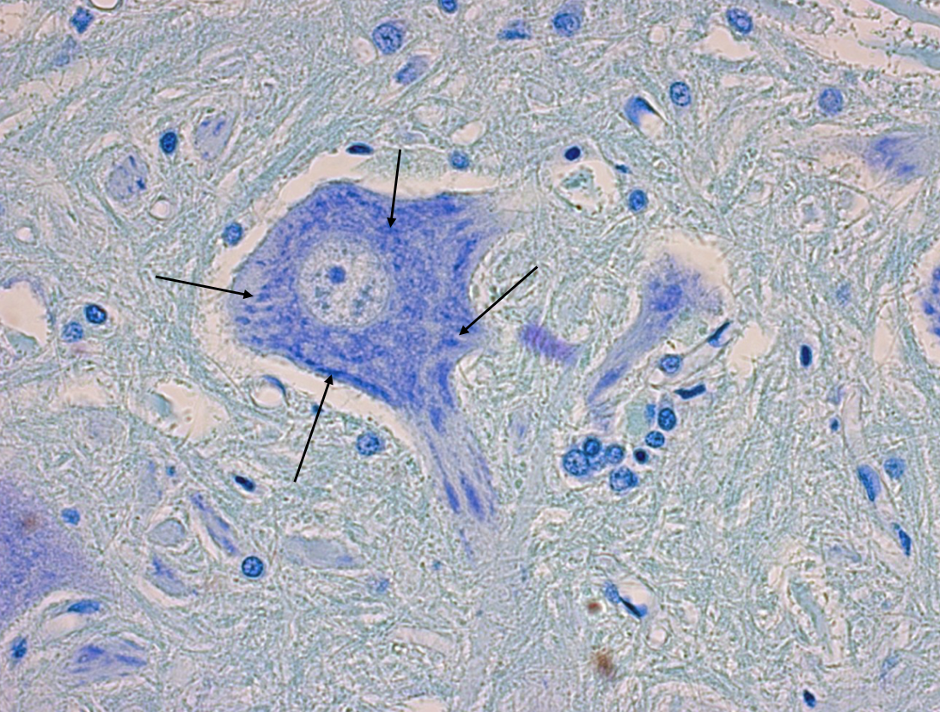

4

Nissl substance / nissl bodies at arrow tipis